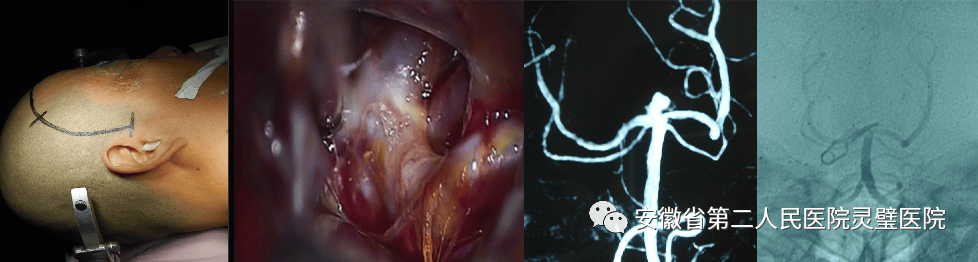

三、脑血管病的综合治疗技术

脑血管病亚专业组紧跟国际前沿,目前全面开展颅内动脉瘤、脑动静脉畸形、硬脑膜动静脉瘘等脑血管病的外科及血管内治疗,尤其对复杂颅内动脉瘤,灵活运用支架及球囊辅助、双微导管、液态栓塞剂栓塞、覆膜支架等技术,取得良好效果。开展烟雾病血管搭桥、颈内内膜剥脱术等脑血管外科手术。

手术夹闭基底动脉尖端动脉瘤

颈内动脉内膜剥脱术

烟雾病行血管搭桥+硬膜翻转+颞肌贴敷术